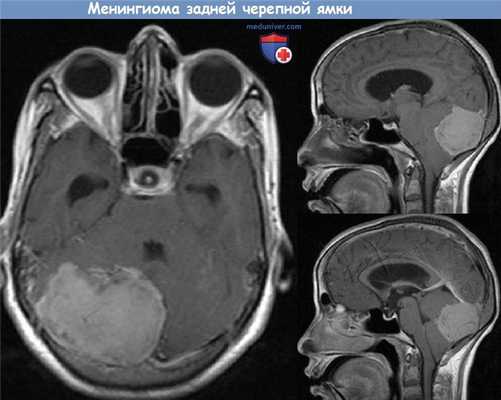

При опухоли типа, А в дообследование включали МСКТ височных костей, а также аудиологическое исследование. При большей распространенности новообразования (тип В, С, D) всем пациентам обязательно проводили МСКТ и МРТ височных костей с контрастированием. Пример МРТ представлен на рисунке.

МРТ основания черепа. Гломусная опухоль c распространением в заднюю черепную ямку (стрелки). а — коронарная проекция; б — аксиальная проекция.